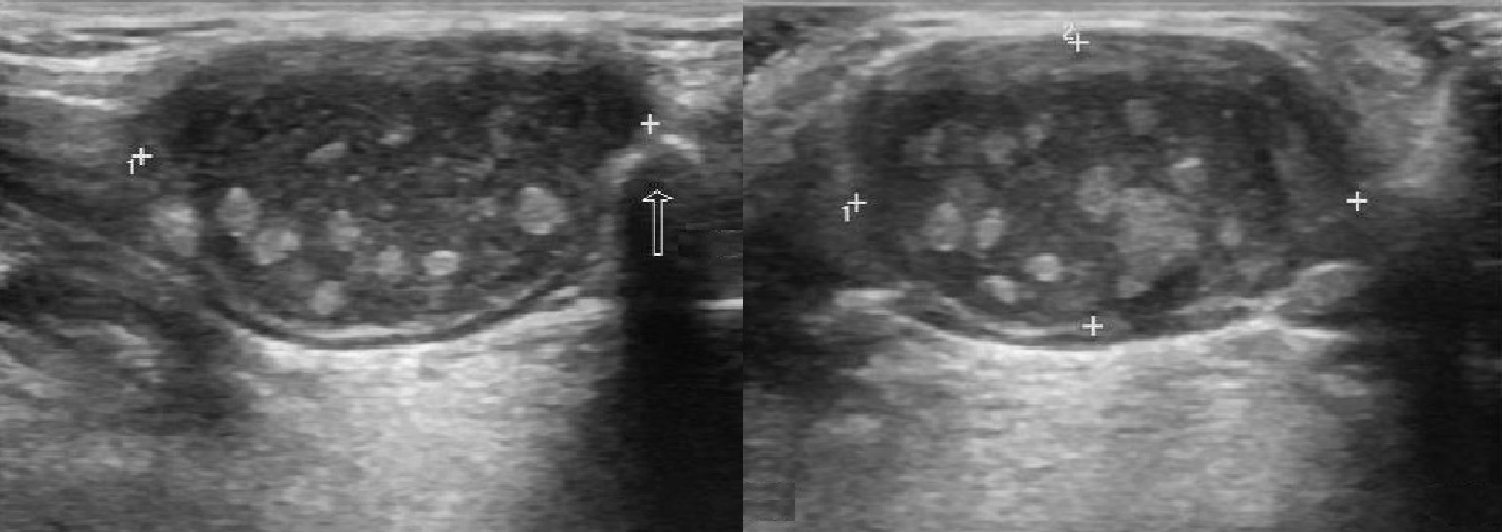

УЗИ лимфоузлов при лимфоме Ходжкина

Раздел: Образы вокруг